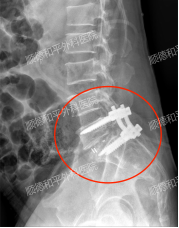

手术过程顺利,成功实施了“L5椎体滑脱伴椎管狭窄后路切开椎管扩大减压+椎间盘摘除+神经根松解+椎间植骨融合内固定术(备:髂骨取骨术)。”

术后,由于解除了神经压迫,患者双腿麻木感即刻消失,仅留有轻微酸胀感,需要时间恢复,这一良好的手术效果让患者和家属悬着的心终于放下。